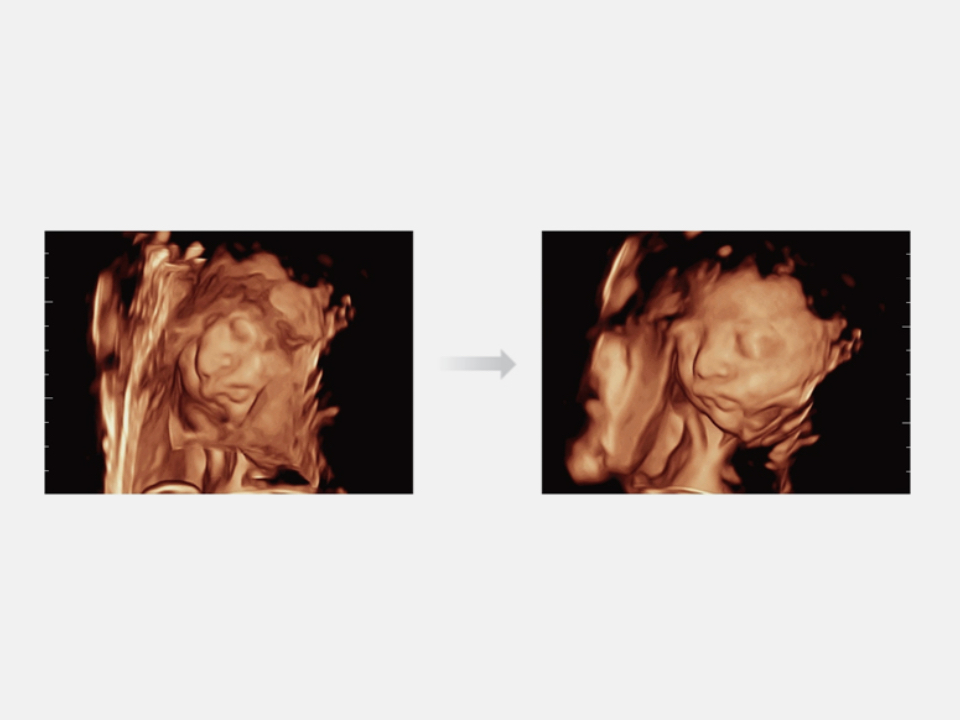

Thanks to the innovative, software-driven ZST+ platform, the Resona series is continuously evolving with the leading-edge technologies to meet the most challenging diagnostic demands in womenŌĆÖs health practice. More importantly, it is designed with the understanding that the wisdom of experts is always precious, and you need more intelligent partner for enhanced speed and confidence. Finally, Resona series with Zone Intelligence provides a total solution to help you with diagnostic confidence, efficiency, and standardization across different diagnostic challenges in todayŌĆÖs demanding and overburden hospital environment.